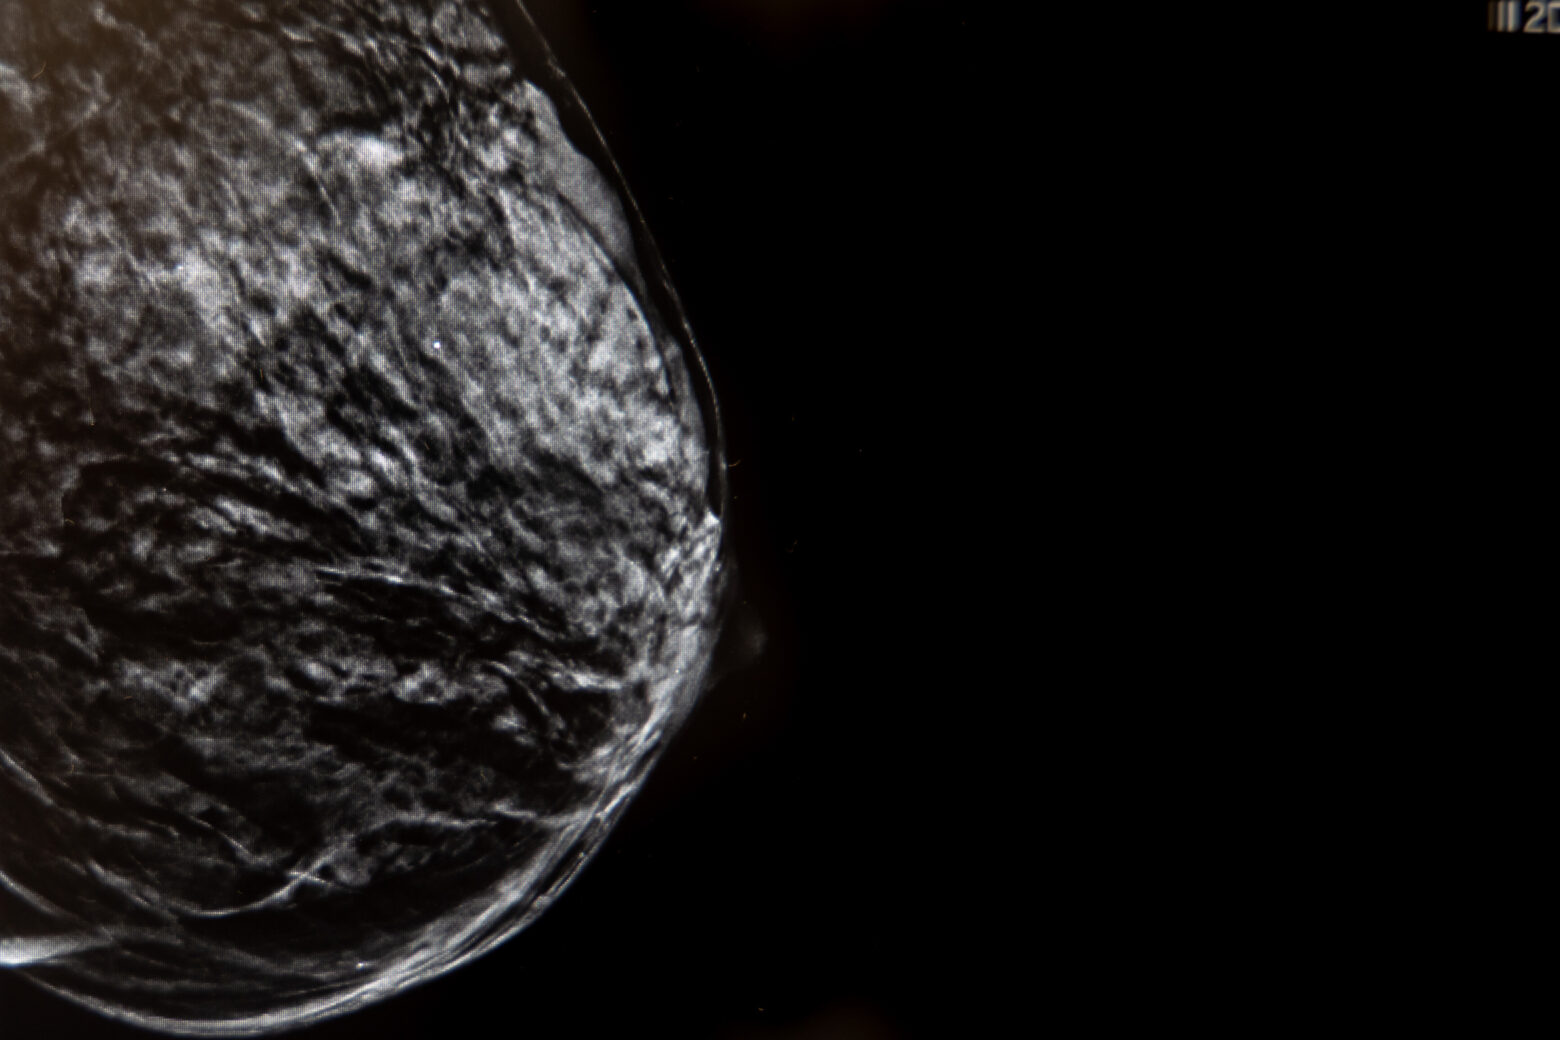

Uno de los mayores avances en el diagnóstico mamario es la imagen 3D (Tomosíntesis) que consiste en la adquisición de imágenes de baja dosis de radiación.

La mamografía con contraste, también llamada mamografía espectral con realce (CEM), es una técnica de imagen mamaria avanzada que combina la mamografía digital con la administración intravenosa de un contraste yodado y un procesamiento digital avanzado.